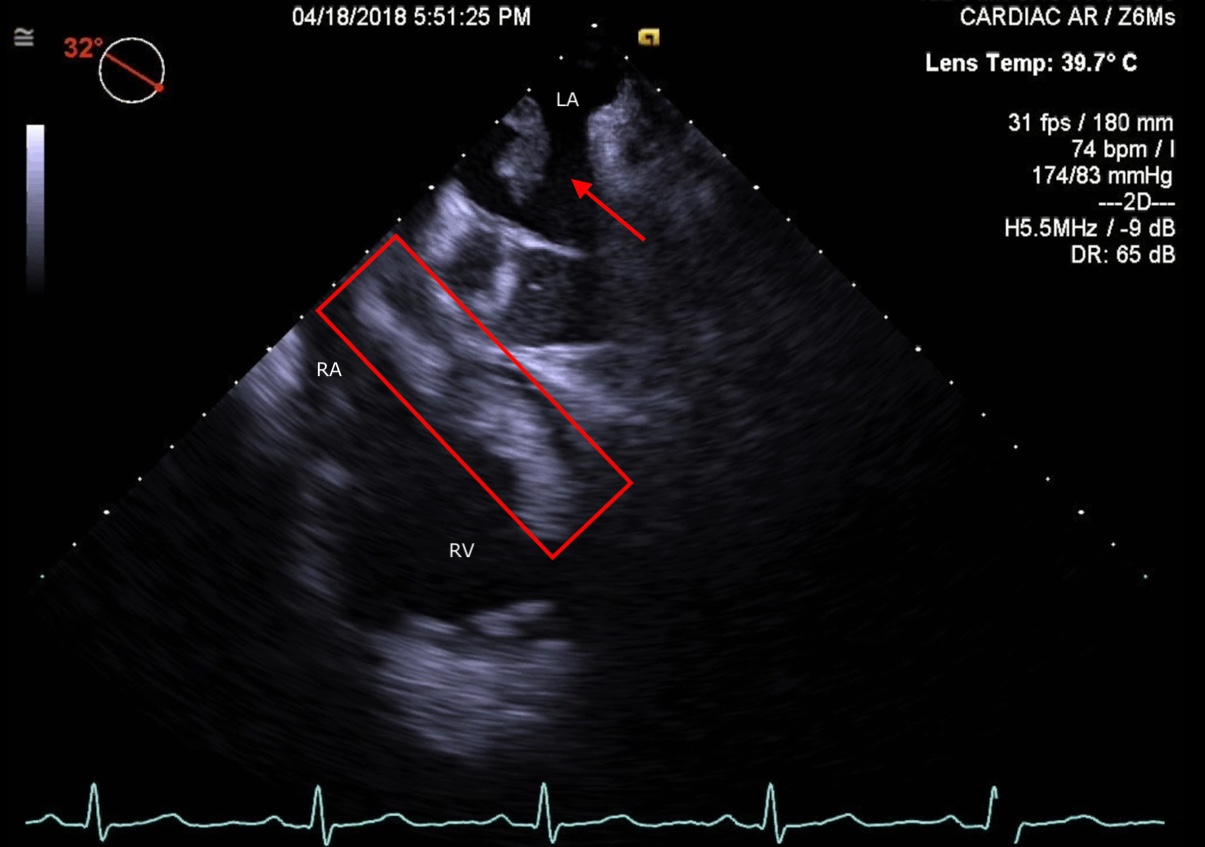

Figure 3. TEE Image depicting thrombus extension into the right ventricle and thrombi in the atria (marked in red). Abbreviations: LA, left atrium; RA, right atrium; RV, right ventricle.

Transesophageal echocardiography (TEE) demonstrated thrombi in transit through a patent foramen ovale (PFO) (Figures 1 and 2; Video 1) and showed the presence of thrombi in all 4 chambers of the heart (Figure 3; Video 2).